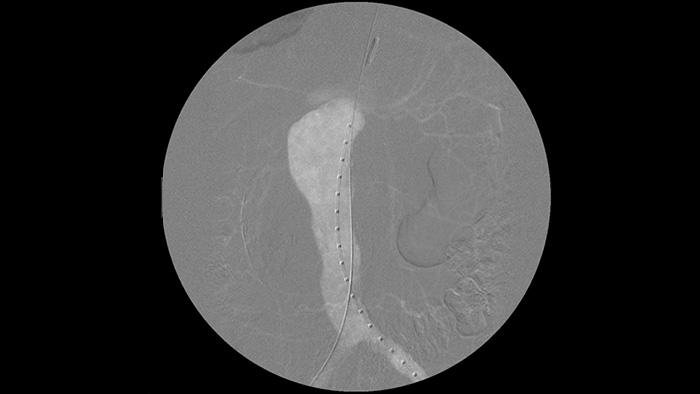

Il est plus facile de voir un guide par rapport à notre ancien système. Vous pouvez désormais voir la pointe et l’angle du fil qui se déroule, même avec des fils de 0,35 mm.

En effet, le système Zenition compense ce qui est métallique et ce qui bouge."

Améliorez la visibilité des vaisseaux sinueux avec les options de contraste à base d’iode et de CO2. Contrôlez facilement les injections depuis la table. Pour les patients souffrant d’insuffisance rénale, vous pouvez utiliser l’option CO2 pour visualiser facilement les petits vaisseaux sans utiliser de produit de contraste iodé.